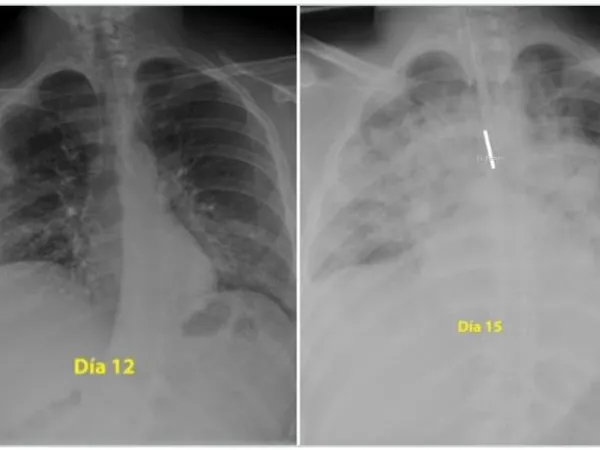

Un medic pneumolog din Spania a postat pe Twitter două radiografii care arată cum s-au degradat, în numai trei zile, plămânii unui tânăr de 28 de ani care a făcut o formă gravă de Covid-19.

Prima fotografie este în a 12-a zi de boală a tânărului, a doua îi înfățișează plămânii în a 15-a zi de boală.

„Pentru cei care cred că sunt nemuritori și continuă să iasă în parc fără să acorde atenție ordinului de a rămâne acasă, acestea sunt radiografiile unui băiat de 28 de ani intubat la Terapie Intensivă în spitalul meu, pentru #coronavirus. Indiciu: plămânii sunt negri, albul este pneumonie”, a scris medicul pe Twitter, potrivit Digi24.